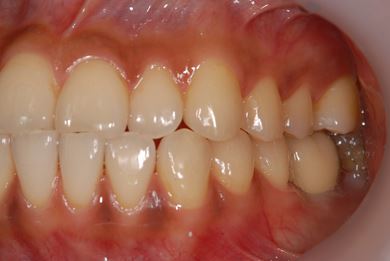

| 性別/年齢 | 女性 / 27歳 | ||||||||||||||||||||||||||||||||

| 治療方針 | インプラント治療にて、機能的・審美的回復を行う。 | ||||||||||||||||||||||||||||||||

| 治療内容 | インプラント1本、メタルボンドセラミッククラウン1本 | ||||||||||||||||||||||||||||||||

| 総治療費 | 252,000円 | ||||||||||||||||||||||||||||||||

| 治療期間 | 4ヶ月 |